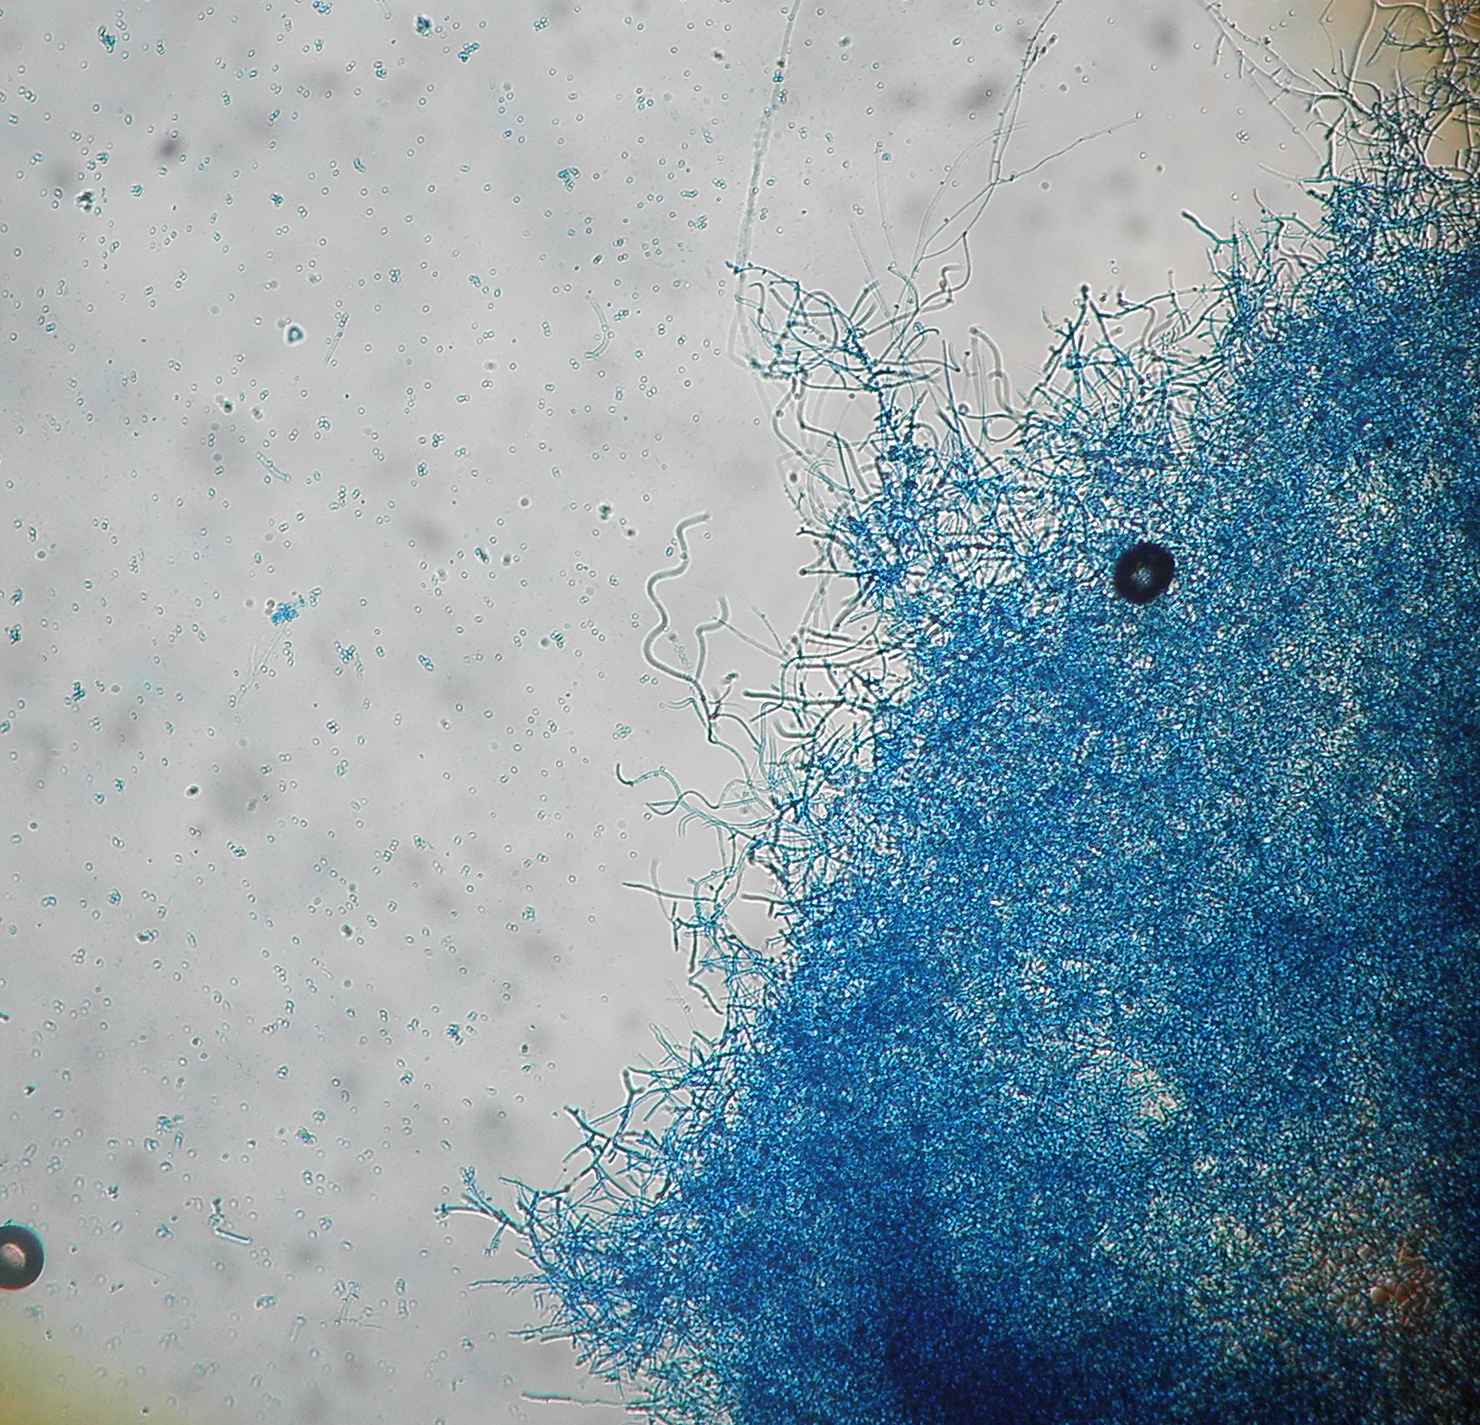

Aspeto microscópico tipico: microconideos abundantes e arredondados dispostos fazendo lembrar cachos de uva.

Hifas espiraladas (azul lactofenol).